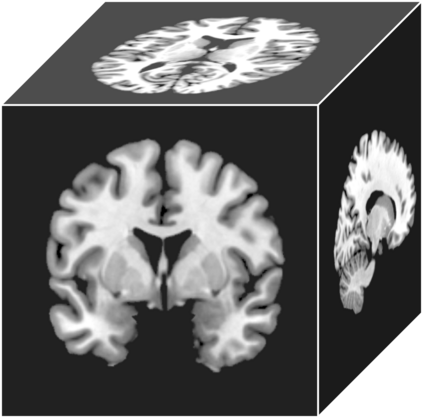

Transfer learning has been widely utilized to mitigate the data scarcity problem in the field of Alzheimer's disease (AD). Conventional transfer learning relies on re-using models trained on AD-irrelevant tasks such as natural image classification. However, it often leads to negative transfer due to the discrepancy between the non-medical source and target medical domains. To address this, we present evidence-empowered transfer learning for AD diagnosis. Unlike conventional approaches, we leverage an AD-relevant auxiliary task, namely morphological change prediction, without requiring additional MRI data. In this auxiliary task, the diagnosis model learns the evidential and transferable knowledge from morphological features in MRI scans. Experimental results demonstrate that our framework is not only effective in improving detection performance regardless of model capacity, but also more data-efficient and faithful.